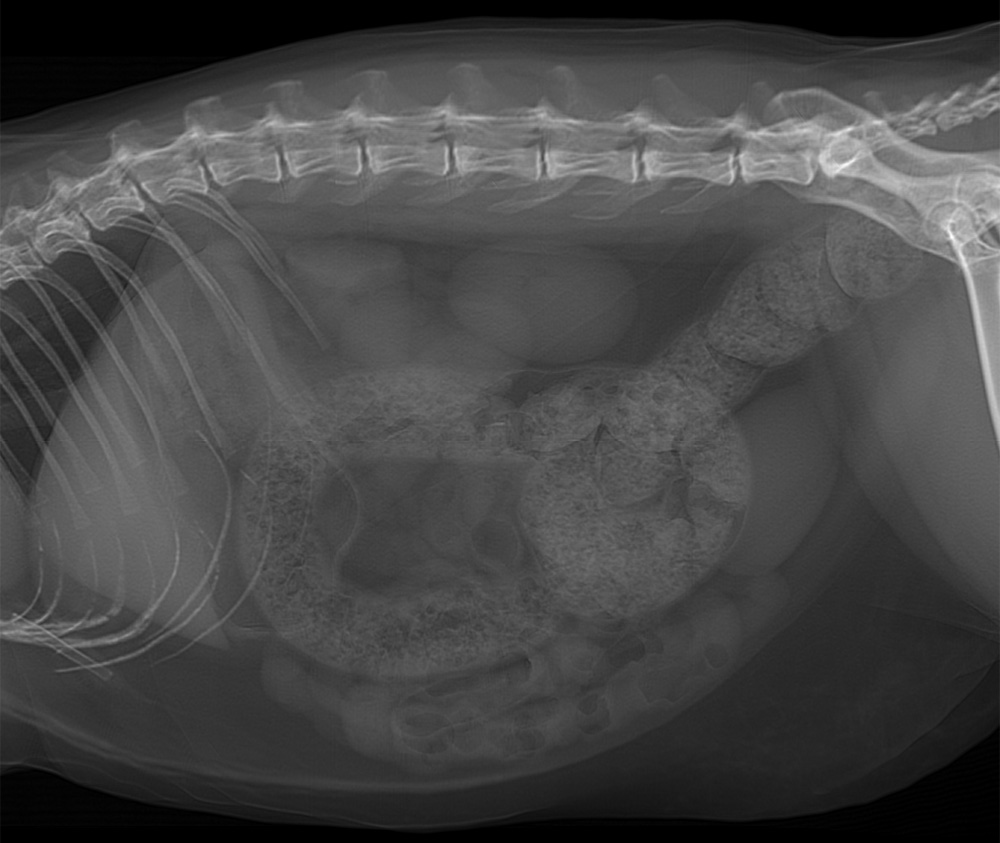

Abdomen de chat – Simulation radiographique

Latérale droite